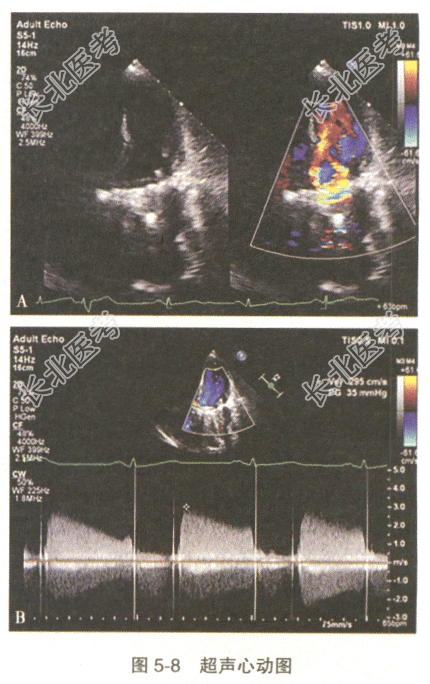

患者,女性,51岁。5天前无诱因出现吐词不清、四肢无力、口角歪斜。急诊入院查体:神志模糊、言语不能,颈软,左下肢病理征(+)。CT检查提示脑出血,患者10年前行二尖瓣及主动脉瓣机械瓣置换术,常规服用华法林,因脑出血停用抗凝药3天,现患者感胸闷、心慌。行超声心动图检查见图5-8:二尖瓣位人工瓣口舒张期见两束血流信号,测得峰速3.0m/s,压差35mmHg。

- 多项选择题1.根据上述超声图像,此患者最可能的诊断是

A、人工主动脉瓣关闭不全

B、人工二尖瓣瓣周漏

C、人工主动脉瓣狭窄

D、人工二尖瓣撕脱

E、人工二尖瓣狭窄